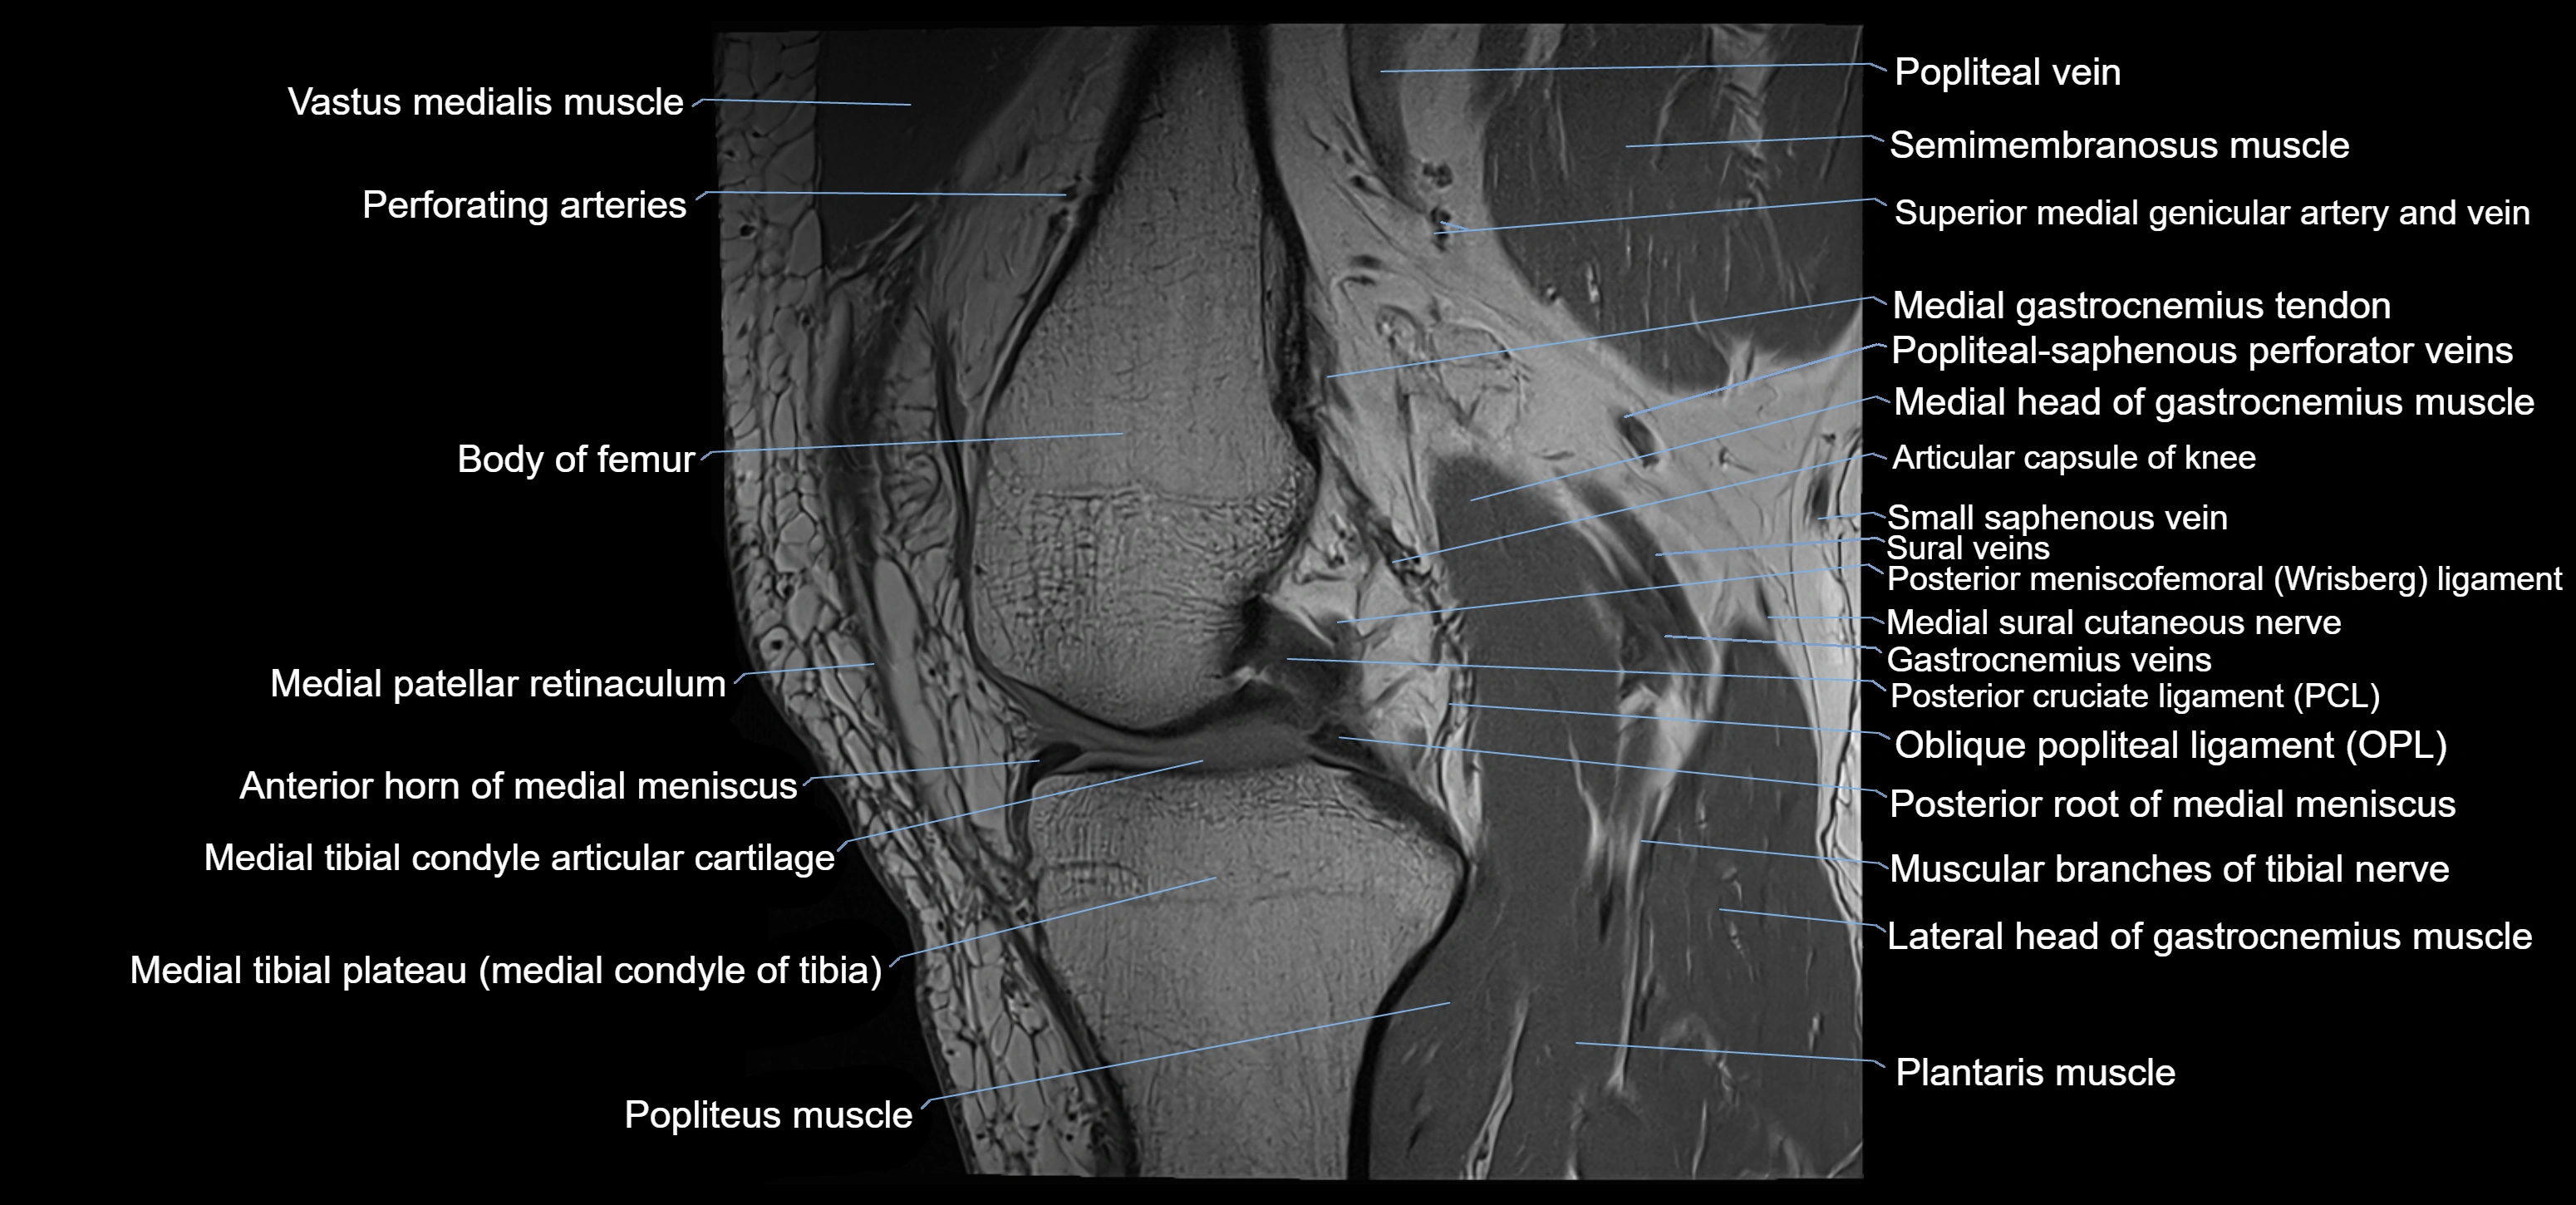

- Anterior horn of medial meniscus

- Body of medial meniscus

- Medial condyle of femur

- Medial condyle of tibia

- Medial gastrocnemius tendon

- Medial head of gastrocnemius muscle

- Medial patellar retinaculum

- Medial tibial plateau

- Muscular branches of tibial nerve

- Oblique popliteal ligament

- Plantaris muscle

- Popliteal artery

- Popliteal vein

- Popliteus muscle

- Posterior cruciate ligament

- Posterior horn of medial meniscus

- Posterior meniscofemoral ligament

- Posterior root of medial meniscus

- Small saphenous vein

- Superior medial genicular artery

- Vastus medialis muscle